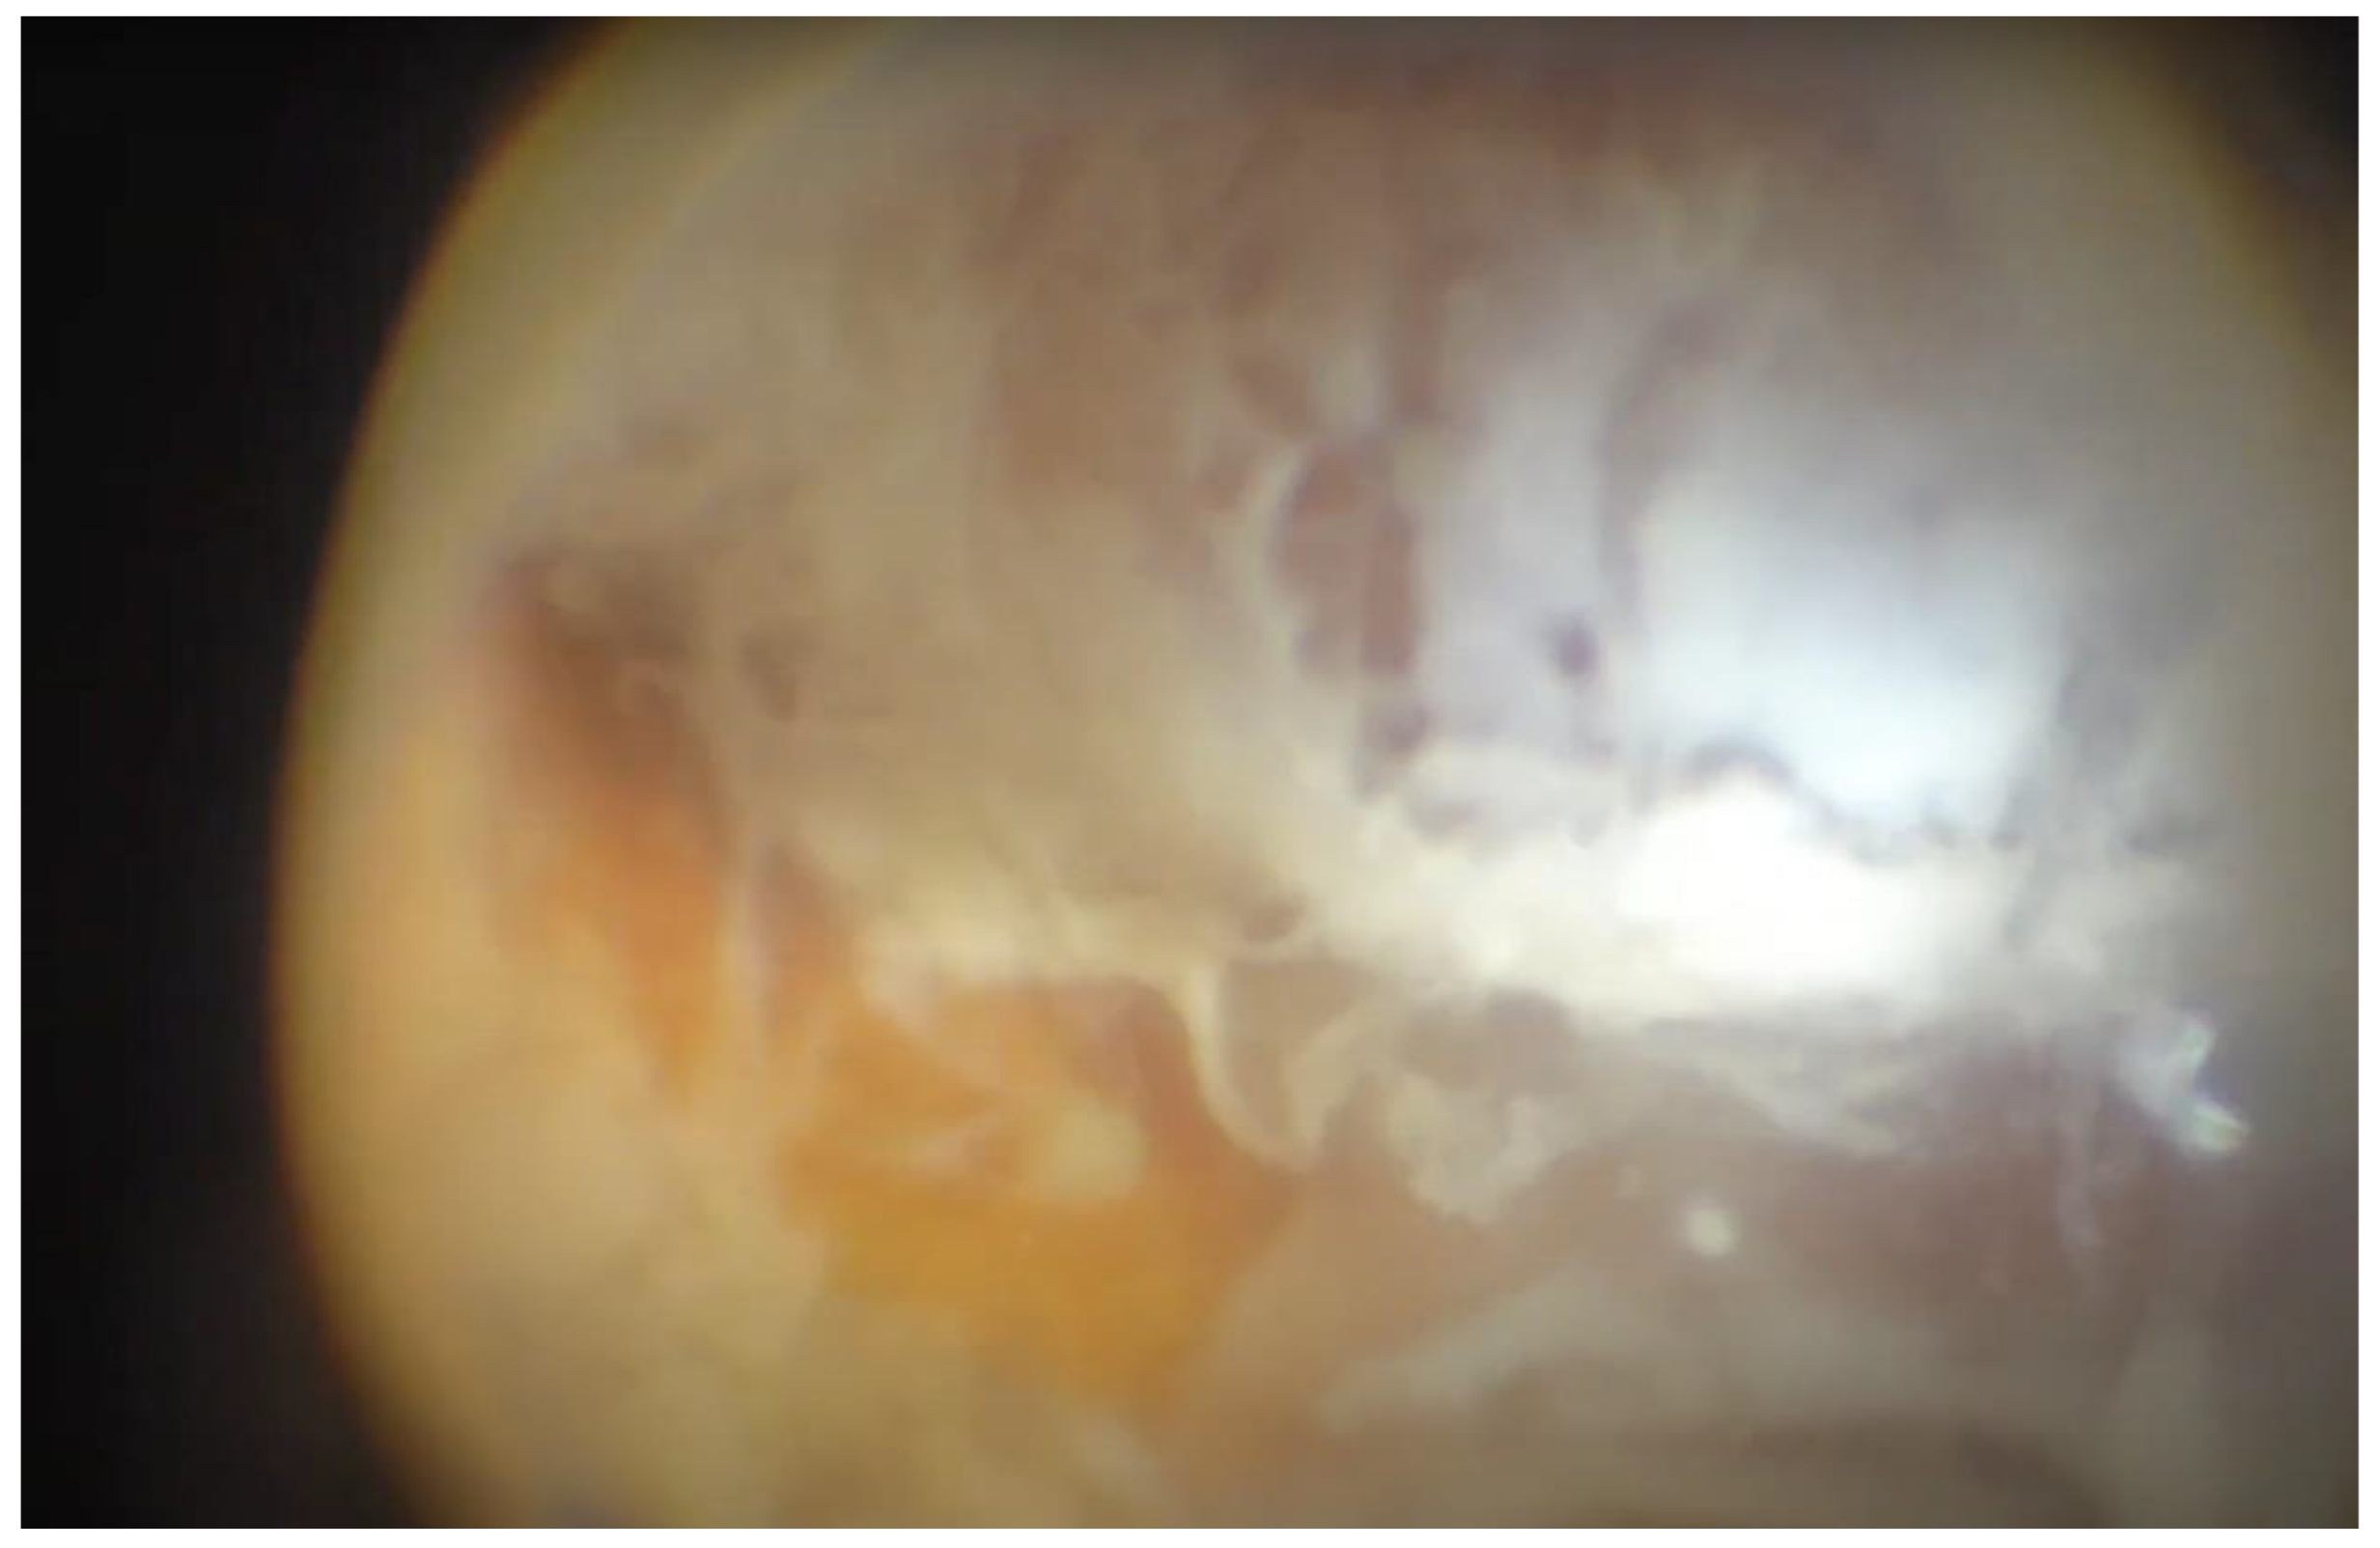

Endophthalmitis (Figure 1) is a rare but severe condition that requires rapid and efficient action to preserve the patient’s vision, eye, and, in cases of highly virulent pathogens, even the patient’s life.

Figure 1. Acute postoperative acute endopthalmitis.